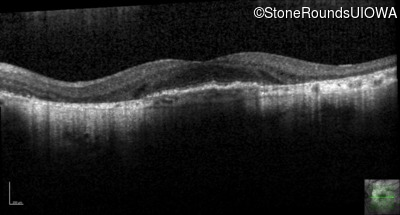

Age at visit: 55 years

Age at visit: 55 years (Visit 2)